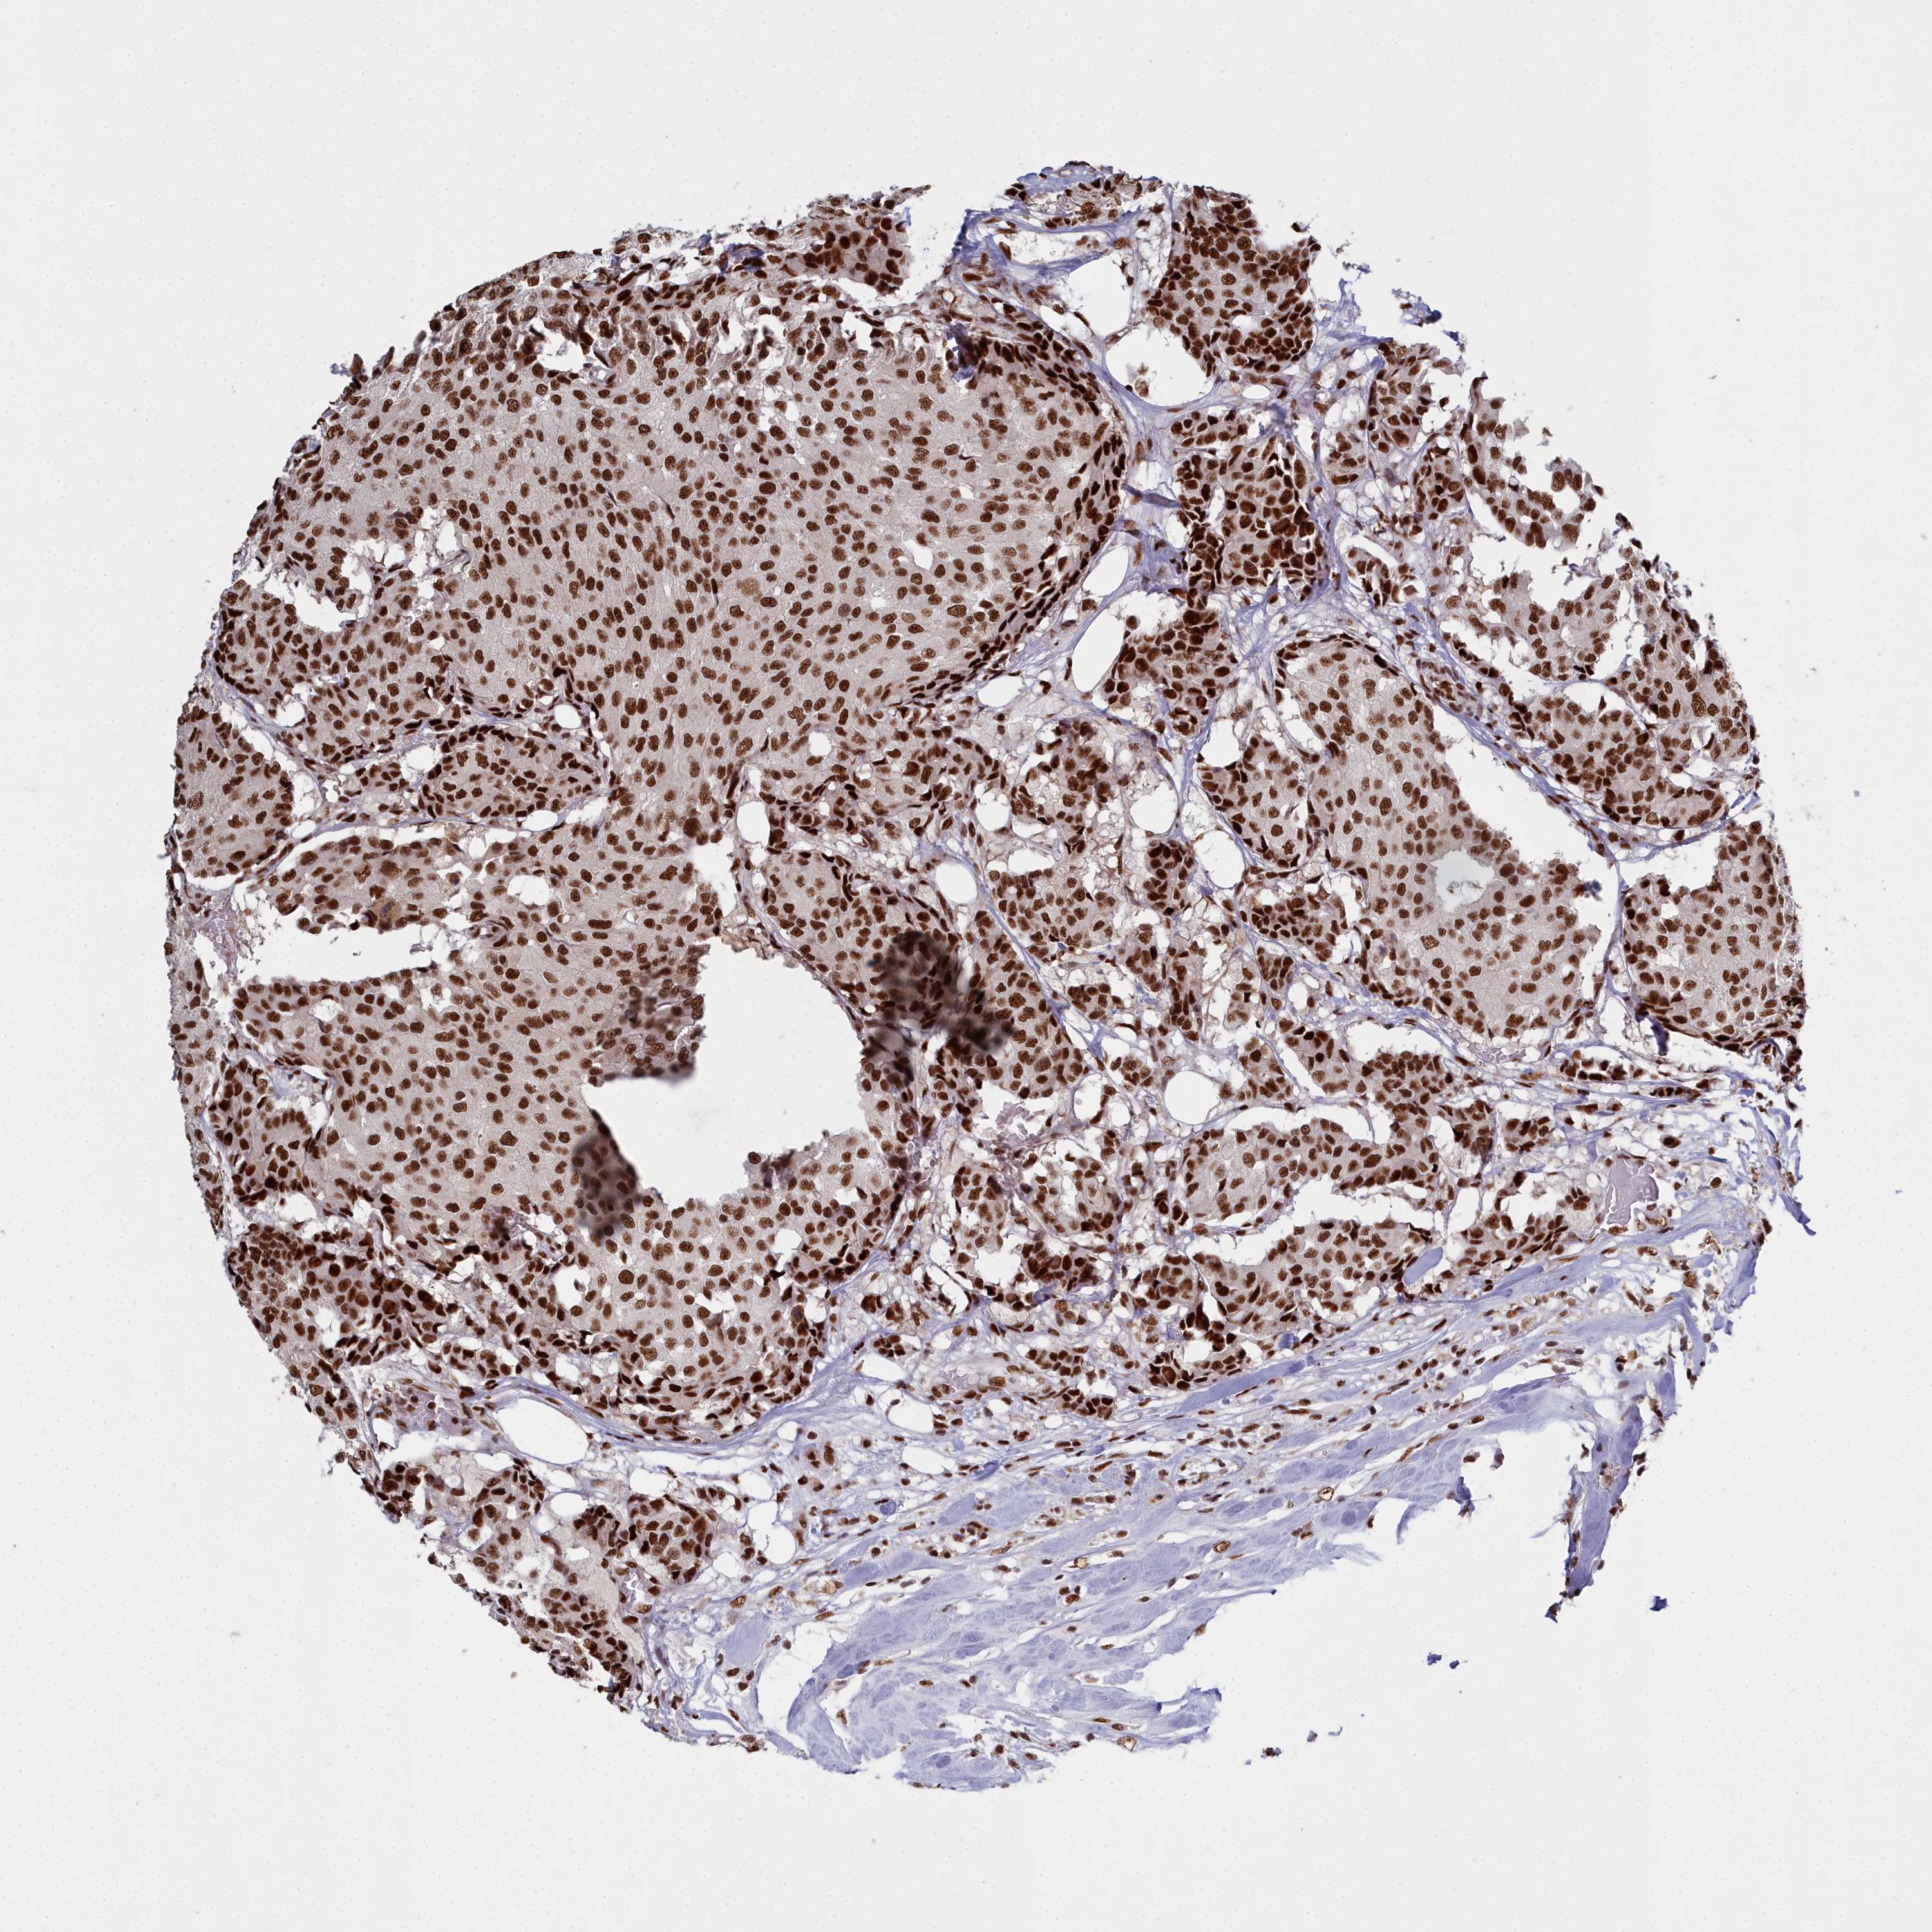

CANCER BREAST CANCER Show tissue menu

BRCA TCGA BRCA VALIDATION PROTEIN EXPRESSION